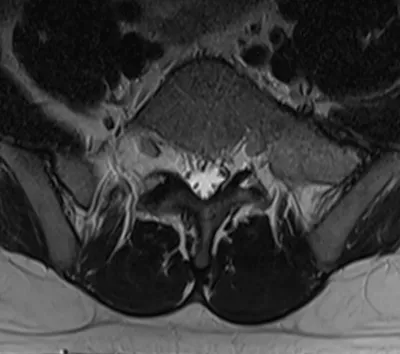

Dysplasia Radiology Images

Browse 5 medical images tagged with dysplasia. This collection includes various imaging modalities for medical education and reference.

- This collection contains 5 radiology images related to dysplasia, including various imaging modalities such as X-rays, MRIs, CT scans, and ultrasound images commonly used in medical diagnosis and education.